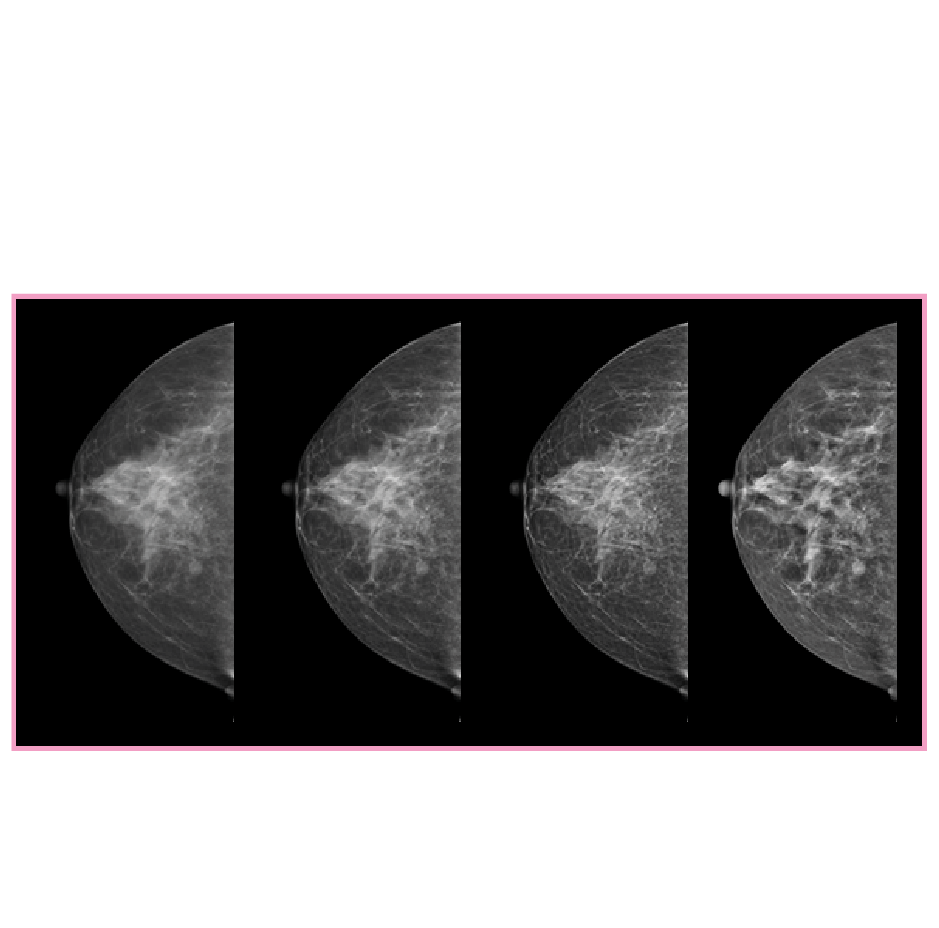

3D Tomosentez (Senographe Pristina 3D)